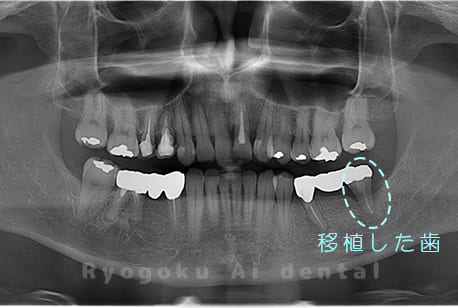

他院で虫歯が大きいため、また、根っこが病気になっているため、親知らずとともに抜歯し、2本インプラントを進めらた患者様です。親知らず(8番)と共に7番目の歯を保存不可能と判断し、2本抜歯を行い、反対側の親知らずのみを1本分移植しました。当初は親知らずの部分までもインプラントを提案されていましたが、噛み合わせの関係上、特に必要ないことを納得していただき、7番目の歯のみに移植治療を行なった患者さんです。